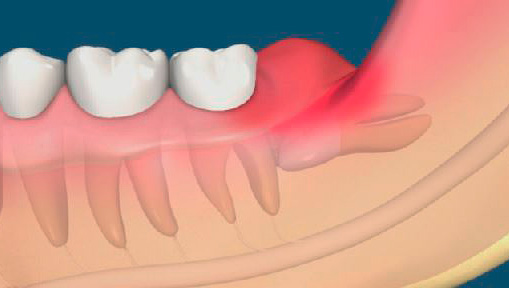

Quando dentano i denti del giudizio, spesso hanno una banale mancanza di spazio: possono crescere lateralmente e verso il vicino più vicino. In generale, i denti del giudizio inferiori sono i più problematici, poiché quando esplodono compaiono di solito uno o due tubercoli, ricoperti di una gomma, come un "cappuccio", sotto il quale, come in un "bidone della spazzatura", il cibo viene costantemente riempito e marcito.

All'inizio, questo si manifesta con l'odore sgradevole di decomposizione dalla bocca e un lieve dolore durante la masticazione di cibi solidi. Presto il dolore alle gengive si intensifica, a volte sorgono sensazioni dolorose nella guancia, vengono provocati denti adiacenti, mascella, gola, orecchio, mal di testa e la febbre può aumentare.

Il dolore provoca non solo una sensazione di "scoppio", che crea un dente del giudizio nelle gengive per analogia con il taglio dei denti da latte nei bambini. C'è la formazione di essudato purulento (semplicemente pus), che non trova una via d'uscita da sotto le gengive e si precipita nel tessuto circostante. Irrita e stringe numerose terminazioni nervose, causando un forte dolore non solo nel dente del giudizio causativo, ma anche irradiando (dando) lungo i rami nervosi ad altri organi e formazioni (guancia, orecchio, gola, ecc.).

La pericoronite si forma sullo sfondo dell'attività della microflora batterica, che trova un ambiente favorevole per la vita e la riproduzione sotto il cappuccio gengivale del dente del giudizio. Oltre alla formazione di essudato purulento sotto la gomma, spesso c'è anche una lesione meccanica alla zona gonfia della gomma che si gonfia a causa dell'infiammazione, coprendo il dente del giudizio, a seguito del quale si formano erosioni e ulcere sulla sua superficie, peggiorando le condizioni dei tessuti circostanti e provocando forti dolori alla gomma e alla guancia.

Dopo alcuni giorni, può verificarsi la pericoronite purulenta, che è caratterizzata da un forte e costante dolore dietro la saggezza dei "sette" adiacente al dente. Può comparire dolore che penetra nell'orecchio e nella tempia e si avverte anche quando si deglutisce come una "mal di gola dentale". Sullo sfondo dell'infiammazione locale, la temperatura corporea sale a circa 37,5 gradi e l'apertura della bocca viene interrotta.